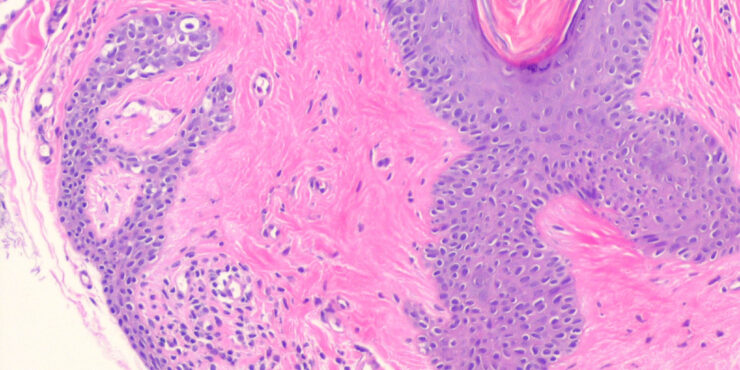

Read MoreFibrous papule (angiofibroma) = حطاطة تليفية =ليفوم وعائي OLYMPUS DIGITAL CAMERA OLYMPUS DIGITAL CAMERA FIBROUS PAPULE Currently, there is some disagreement as to whether fibrous papule represents a neoplastic process or a hamartoma.Fibrous papule (perifollicular fibroma) presents mainly as a solitary papule or as several dome-shaped, skin-colored, pigmented, or reddish lesions situated on the face, […]